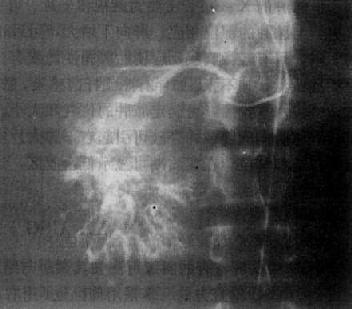

选择性肝动脉影是诊断肝癌的有效方法,它能查出直径小至2cm的肝癌,并确定其范围与数目,供血是否丰富,还可了解有无肝硬化和附近有无肿瘤转移。肝癌的动脉造影可有以下表现:①显示肿瘤血管,表现为肿瘤区内大小不均、形状不规则的血管影或呈“湖样”充盈,其供血动脉增粗;②动脉拉直和移位,动脉边缘不规则且僵硬,系因肿瘤包绕所致;③毛细血管期可见肿瘤染色,呈高密度的结节影;④肝实质期显示为充盈缺损区;⑤有时可形成动静脉瘘,使相邻的门静脉分支早期显影(图4-3-1)。

图4-3-1 原发性肝癌动脉造影

肝动脉造影显示肝内一团巨块状肿瘤血管,大小不均,形态不规则,

其中心呈湖样充盈。供血动脉增粗、迂曲